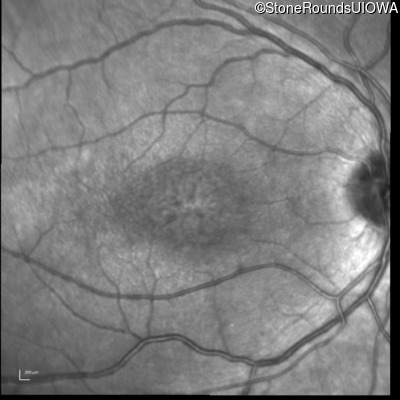

Infrared Fundus Photograph - Right - 20/63 -2

Exemplar

Infrared Fundus Photograph - Left - 20/50